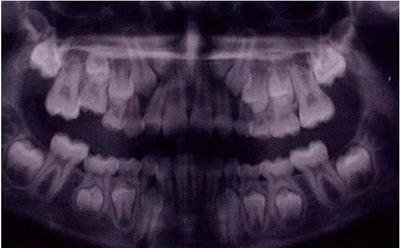

X線片還會顯示合平面呈現(xiàn)出一個臺階,并通常會有一個角度朝向固連牙的角型牙槽骨缺損。(圖5)。許多臨床醫(yī)生更愿意選擇拍攝曲面體層片而不是根尖片,因為考慮到乳牙下沉經(jīng)常會雙側(cè)發(fā)生并合并其它發(fā)育異常,同時也為了確定是否需要正畸治療。臨床檢查和影像學檢查聯(lián)合評估同樣也為了排除其它病因,譬如原發(fā)性的萌出障礙,牙齒嵌入或者其它異常。

文獻直達|乳磨牙下沉的臨床管理

圖4:由于乳牙下沉而導致合平面發(fā)生改變的臨床像

圖5:由于乳牙下沉而導致合平面發(fā)生改變的曲面體層像